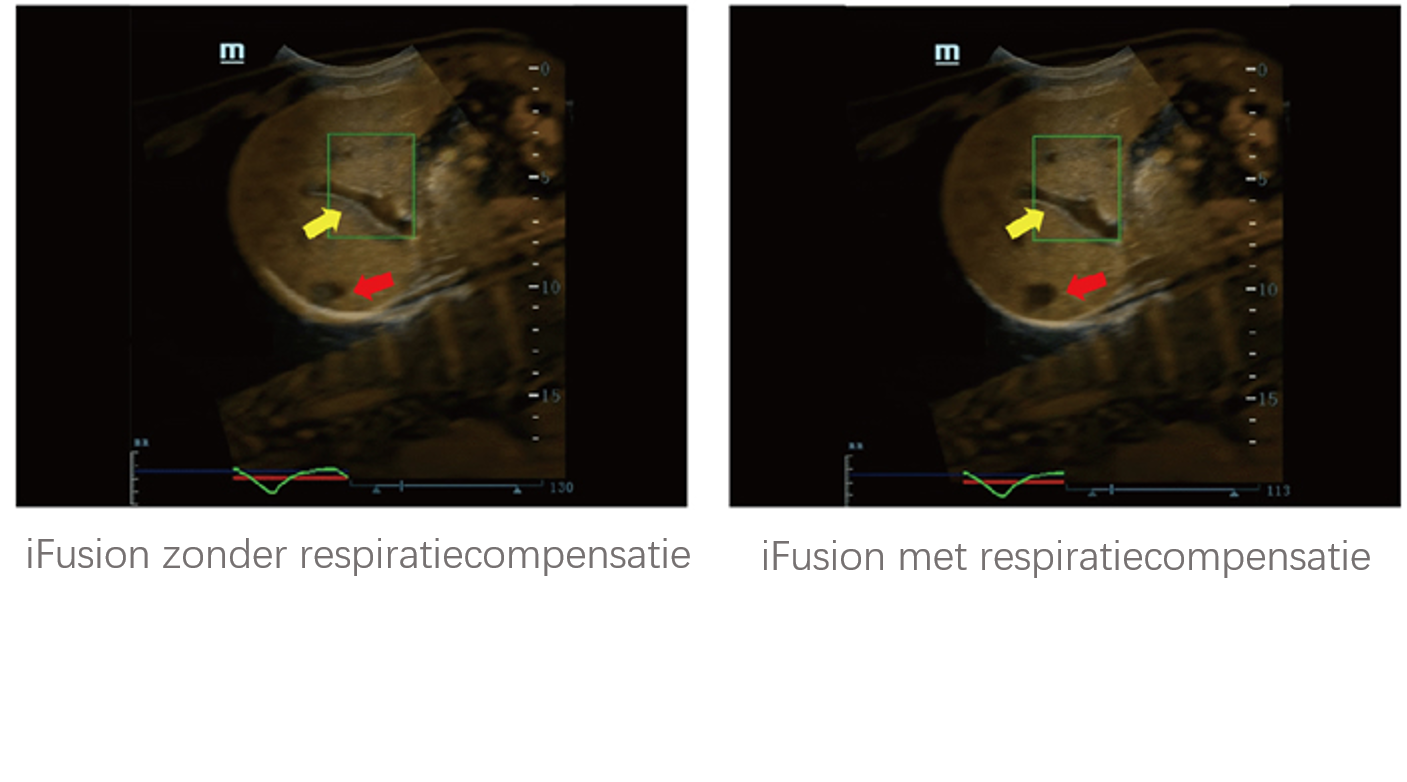

Sinds de oprichting van het bedrijf is Mindray voortdurend op zoek naar nieuwe manieren om het diagnostisch vertrouwen te vergroten. Resona 7 wordt aangestuurd door de meest revolutionaire ZONE Sonography?-technologie. Zijn nieuwe ZST+-tilt de kwaliteit van ultrasoundbeeldvorming naar een hoger niveau door middel van zoneacquisitie en kanaalgegevensverwerking.

Naast de hoogwaardige beeldvormingskwaliteit verbetert de Resona 7 tevens de klinische onderzoeksmogelijkheden met de revolutionaire V Flow voor vasculaire hemodynamische evaluatie, en de intelligentste vlakacquisitie van een 3D-gegevenssets voor de diagnose van het foetale, centrale zenuwstelsel. Met zijn combinatie van de meest intu?tieve, op vingerbewegingen gebaseerde multi-aanrakingsbediening en alle essenti?le klinische functies loopt de Resona 7 voorop in de nieuwe golven van ultrasoundinnovatie.